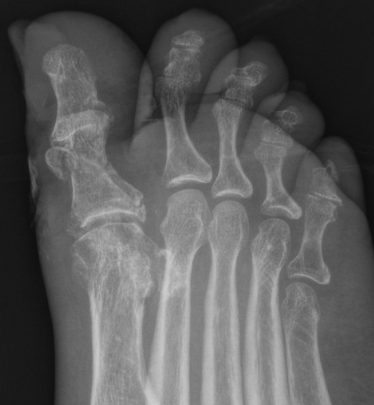

Great toe MTPJ dislocation

Pathology

Hyperdorsiflexion

Metatarsal head dislocates plantar

- tear of plantar plate / disruption bipartite sesamoid

- may buttonhole through capsule / plantar plate

Xray